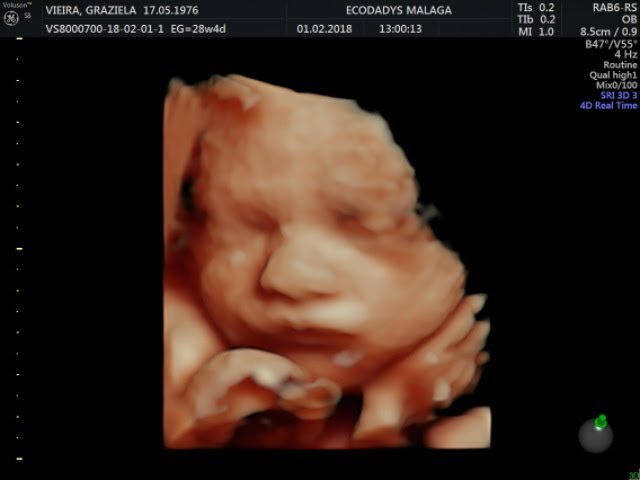

La ecografía 5D es una imagen en tres dimensiones y en tiempo real como la 4D pero en la que el tratamiento de las imágenes en el ordenador permite suavizar las texturas modificar el color de la imagen y aplicar un foco de luz desde diferentes ángulos de forma que se crean luces y sombras y esto le da una imagen más real.

Además de poder obtener excelentes imagenes del rostro y facciones. El ultrasonido en 5D es una imagen en tridimensional live o en tiempo real en la cual las texturas se pueden suavizar cambiar de color y aplicar diferentes focos de luz en distintos ángulos los cuales nos da como resultado una imagen más real. Anatomy survey 6 2 Receive a USB drive with the full session videos and pictures. Your 4D Baby le ofrece a las mujeres embarazadas Ultrasonido 3D 4D en Miami y àreas vecinas el mejor servicio de Ultrasonido 2D 3D 4D y 5D HD así como también el Ultrasonido para determinar el sexo del bebé. Receive your ultrasound images and videos directly to your smartphone today. La ecografía 5D es una imagen en tres dimensiones y en tiempo real como la 4D pero en la que el tratamiento de las imágenes en el ordenador permite suavizar las texturas modificar el color de la imagen y aplicar un foco de luz desde diferentes ángulos de forma que se crean luces y sombras y esto le da una imagen más real. Ecografías 2D 3D 4D y ahora ecografías 5D. Centro Médico De Diagnóstico Por Imágenes en CANCUN. Además de poder obtener excelentes imagenes del rostro y facciones.

Baby Studio Ultrasonido 5D. Además de poder obtener excelentes imagenes del rostro y facciones. See your baby in 2D 3D 4D or 5DHD. El estudio revela con detalle la cara fetal y conformación general descarta malformaciones fetales externas. Confirm your babys gender. La nueva generación de ecógrafos de alta resolución incrementa de manera decisiva la capacidad diagnóstica y la detección de malformaciones fetales. 2217 likes 9 talking about this 111 were here.